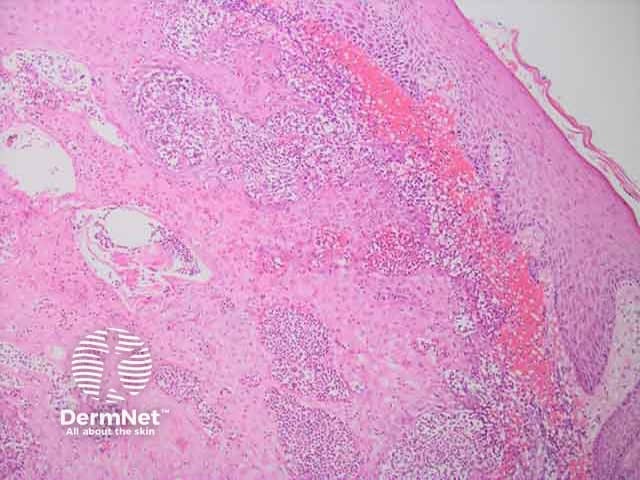

Cutaneous myleoid sarcoma H and E histology

Histopathology: